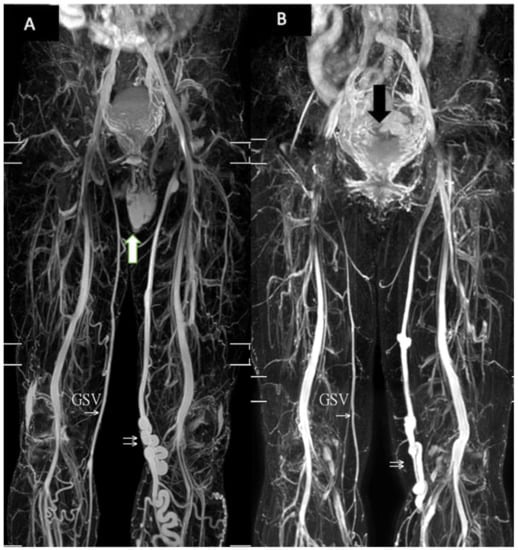

3. Results